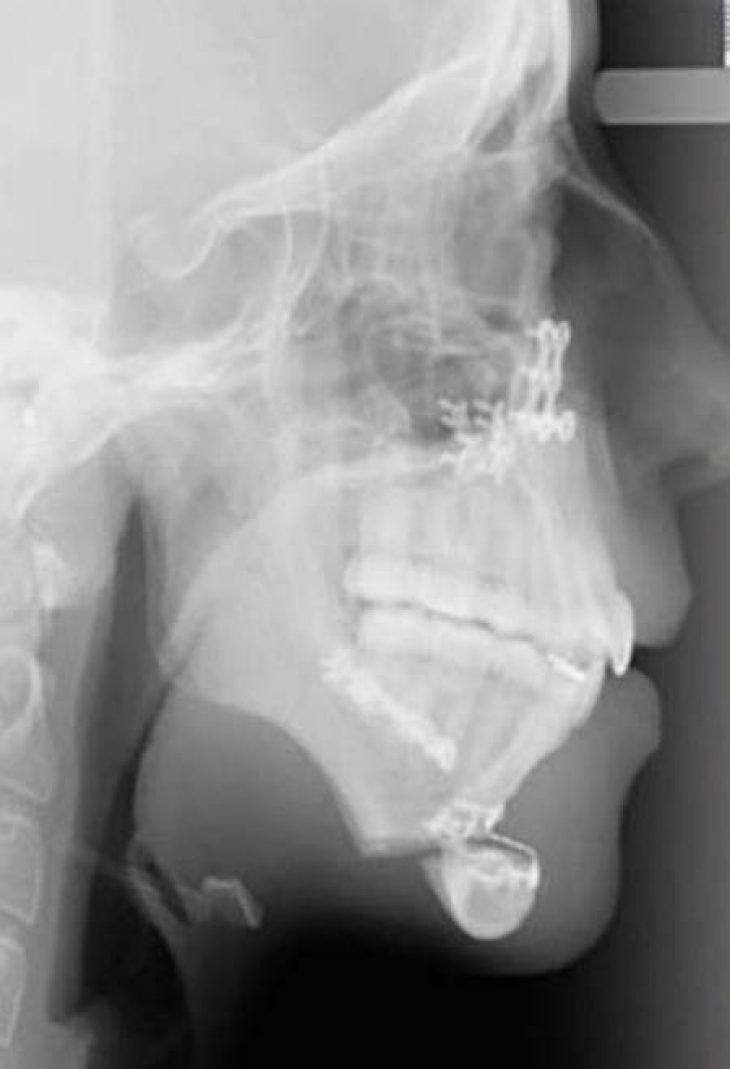

Η ίδια και ο οικογενειακός της περίγυρος αποφάσισαν να μη μείνουν με σταυρωμένα χέρια. Θέλησαν να προχωρήσουν σε μία χειρουργική επέμβαση. Μέσω αυτής της επέμβασης επιδιώκονταν να διορθωθούν όσα ενοχλούσαν την Ellie Jones, τα οποία κρατούσαν και την ψυχολογία της στο ναδίρ.

Η οικογένεια επισκέφθηκε έναν γναθοχειρουργό, ο οποίος βοήθησε στη μεταμόρφωση της Ellie Jones. Το πρώτη χειρουργείο προκάλεσε πολύ πόνο στην 20χρονη. Ήταν ιδιαίτερα δύσκολο σαν χειρουργείο και στο τέλος του έπρεπε να κάνει σωστή διατροφή. Αυτή εμπεριείχε μόνο υγρά για χρονικό διάστημα ενός μηνός, ενώ στο ξεκίνημα δεν μπορούσε να μιλήσει.

Στο χειρουργείο, που ακολούθησε, το οποίο ήταν δεύτερο κατά σειρά μπόρεσε να διορθώσει το πηγούνι της. Έτσι, μπόρεσε να μεταμορφωθεί και να φτιάξει παράλληλα και την ψυχολογία της.

Εικόνες της Ellie Jones πριν και μετά: